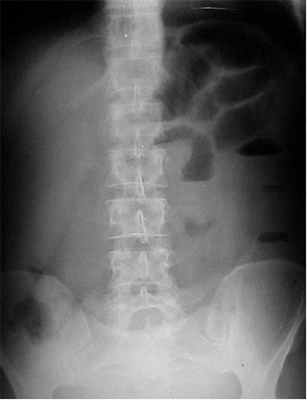

- Рентгенография брюшной полости

Диагноз кишечной непроходимости должен подтверждаться характерной рентгенологической картиной — появлением чаш Клойбера с горизонтальными уровнями жидкости и газа, которые могут располагаться в виде арок на обзорных рентгенограммах брюшной полости. Необходимо отметить, что при пищевых токсикоинфекциях в кишечнике может быть много газа, но он располагается беспорядочно вдоль всей кишки. При этом отсутствуют четкие контуры характерные для непроходимости. '

1. Рентгенологическое обследование является основным специальным методом диагностики ОКН. Обзорная рентгенография брюшной полости должна проводиться при малейшем подозрении на ОКН. При этом выявляется ряд признаков. В норме газ имеется в ободочной кишке. Появление газа в тонкой кишке указывает на непроходимость. Характер скопления газа в просвете кишечника различается при разных вариантах КН (рис. 1). Рисунок 1. Схема скопления газа в просвете кишечника при разных вариантах КН. а - высокая тонкокишечная непроходимость. Возможно наличие единичных горизонтальных уровней жидкости и газа. Наличие газа в толстой кишке не характерно Рисунок 1. Схема скопления газа в просвете кишечника при разных вариантах КН. б - низкая тонкокишечная непроходимость. Обычно видны множественные горизонтальные уровни жидкости и газа (чаши Клойберга). Наличие газа в толстой кишке не характерно Рисунок 1. Схема скопления газа в просвете кишечника при разных вариантах КН. в - странгуляционная кишечная непроходимость. Могут быть как единичные, так и множественные горизонтальные уровни жидкости и газа. Наличие газа в толстой кишке не характерно. Обычно по снимкам удается определить, петли какой кишки - тонкой, толстой или обеих - растянуты газом. При наличии газа в тонкой кишке хорошо видны спиралевидные складки слизистой оболочки (Керкринговы складки), занимающие весь поперечник кишки.

На рентгенограммах, полученных в положении стоя или лежа на боку, обычно видны горизонтальные уровни жидкости и газа (рис. 2). Рисунок 2. Обзорная рентгенограмма брюшной полости. Видны чаши Клойбера, уровни жидкости. Заполненные газом кишечные петли имеют вид опрокинутых чаш (чаши Клойбера). Они появляются при странгуляции через 1-2 ч после начала заболевания, при обтурации - через 3-5 ч. По размерам чаш Клойбера, их форме и локализации можно судить об уровне непроходимости.